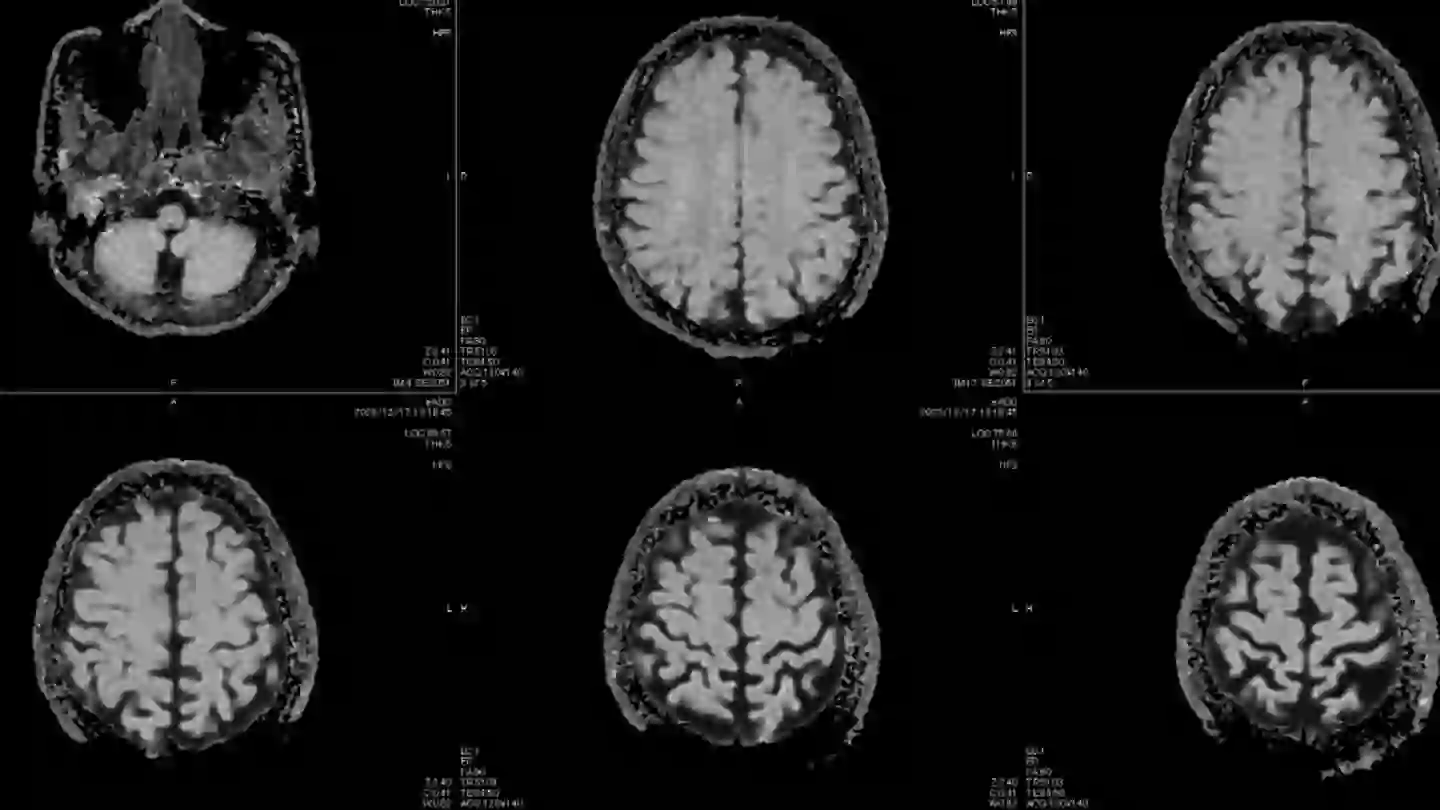

Mass General Brigham Newton-Wellesley Hospital recently came under scrutiny after five nurses from the maternity unit were diagnosed with benign tumors. These tumors, which include three brain tumors and two meningiomas, were all discovered in individuals who had worked in close proximity to each other. A benign tumor is a non-cancerous growth that is typically slow-growing and doesn’t spread to other areas of the body. However, depending on its size, a benign tumor can press on surrounding tissues and organs, requiring surgical intervention for removal.

According to the Mayo Clinic, meningiomas are the most common type of tumor that forms in the head. Meningiomas grow from the membranes surrounding the brain and spinal cord, known as the meninges. While a meningioma is not technically a brain tumor, it can press against the brain, nerves, and blood vessels, leading to symptoms that require medical attention.